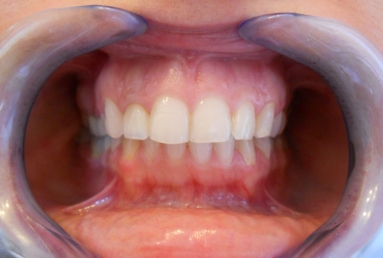

Initial clinical situation: upper lateral incisor with a big composite filling and an old root canal treatment. that caused in time a grey discoloration of the tooth. Internal tooth whitening would not give a good result in this case, because of the composite filling, and also because the whitening is not stable in time. This is why the decision was to restore the tooth with a very esthetic full ceramic crown, which does not change colour in time, at the same time protetcting a non vital tooth against fracture.